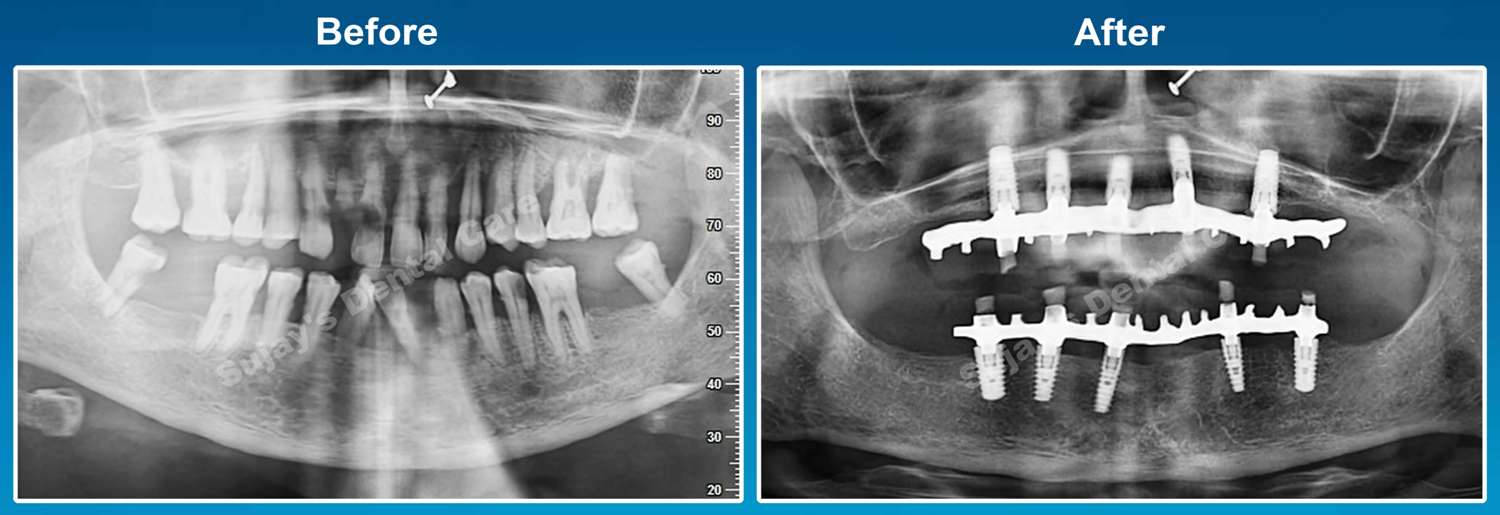

Before & After